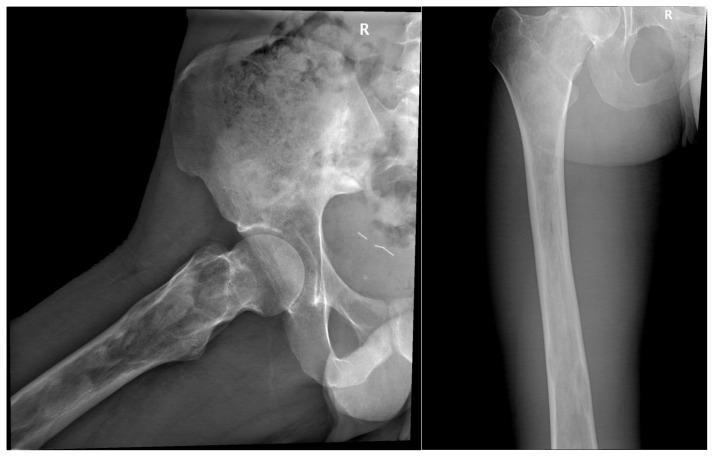

McCune-Albright syndrome is a rare sporadic disease characterized by bone fibrous dysplasia, café-au-lait skin spots and a variable association of hyperfunctional endocrine disorders. Fibrous dysplasia (FD), which can involve the craniofacial, axial, and appendicular skeleton, may range from an isolated, asymptomatic monostotic lesion to a severe disabling polyostotic disease involving the entire skeleton. A twenty-five-year old male patient presented to our clinic with recently developed heart palpitations. He had also been feeling pain in the right femur since he was younger, without any trauma history, leading to difficulties of ambulation and limping occasionally. His physical examination revealed café-au-lait spots with irregular borders and right testicular agenesis. Laboratory findings identified hyperthyroidism with hyperparathyroidism. Radiographs of the pelvis revealed multiple lytic lesions of the right femur and magnetic resonance imaging (MRI) characterized these lesions as specific to fibrous dysplasia of the bone, without any insufficiency fracture at this level. The association of café-au-lait skin spots with bone fibrous dysplasia, and hyperthyroidism in this patient suggested the diagnosis of McCune - Albright syndrome.

McCune - Albright综合征是一种罕见的散发性疾病,其特征为骨纤维发育不良、咖啡斑皮肤斑点以及多种功能性内分泌紊乱。纤维发育不良(FD)可累及颅面骨、中轴骨和四肢骨骼,范围从孤立的无症状单骨病变到累及整个骨骼的严重致残性多骨疾病。一名25岁男性患者因近期出现心悸前来我院就诊。他自幼右股骨就一直疼痛,无任何外伤史,导致行走困难且偶尔跛行。体格检查发现边界不规则的咖啡斑以及右侧睾丸发育不全。实验室检查结果显示患有甲状腺功能亢进和甲状旁腺功能亢进。骨盆X线片显示右股骨有多个溶骨性病变,磁共振成像(MRI)将这些病变特征化为特定的骨纤维发育不良,在此层面无任何应力性骨折。该患者咖啡斑皮肤斑点与骨纤维发育不良及甲状腺功能亢进的关联提示了McCune - Albright综合征的诊断。